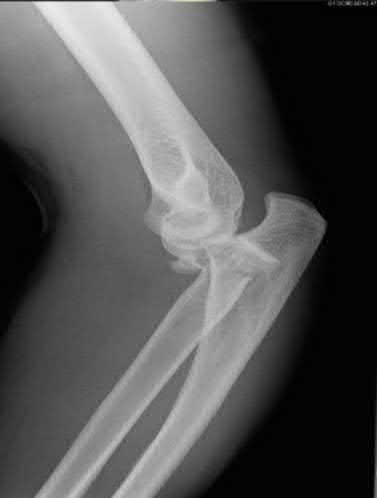

A 45-year-old male is involved in a high-speed motor vehicle collision and presents with the cervical spine radiograph findings typical of traumatic spondylolisthesis of the axis.

Which of the following describes the primary mechanism of injury for this specific fracture pattern (Hangman's fracture)?

Explanation

A 'Hangman's fracture' is a traumatic spondylolisthesis of the axis (C2) involving fractures through the pars interarticularis. The classical mechanism of injury in modern trauma (e.g., unrestrained passenger hitting the windshield) is hyperextension and axial loading. Flexion-distraction typically causes Chance fractures, while flexion-compression typically causes anterior wedge or teardrop fractures.